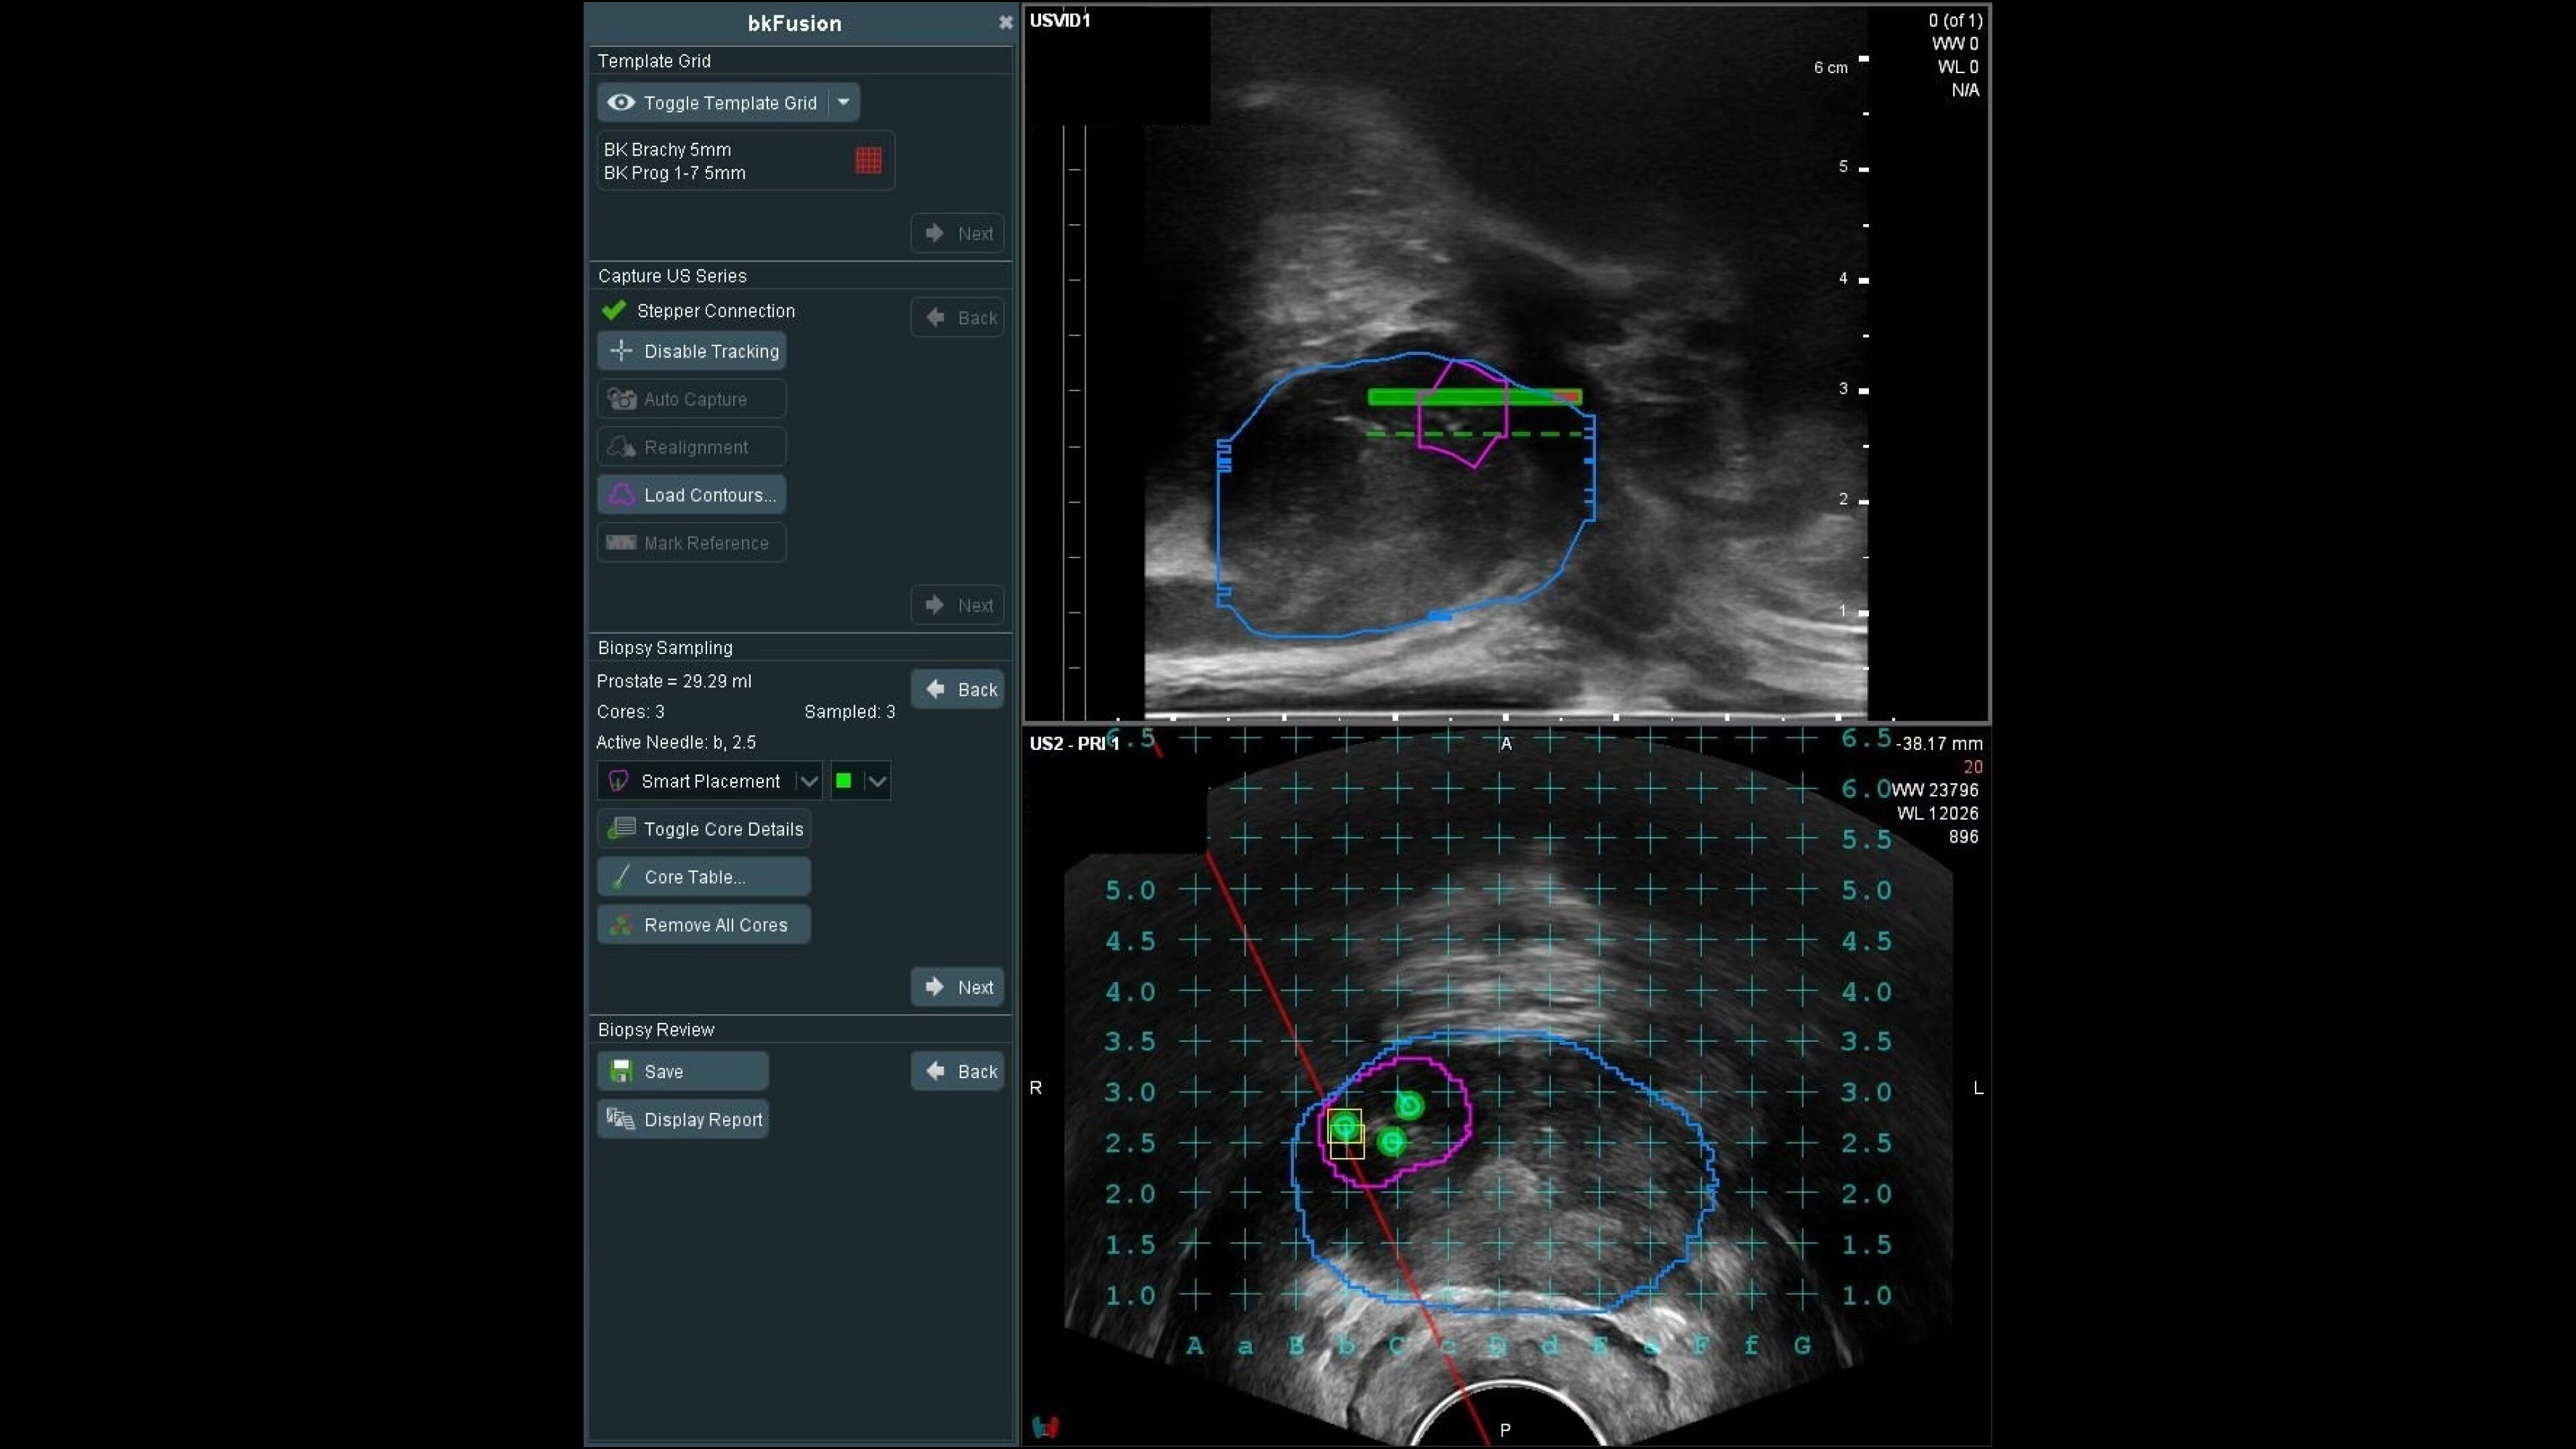

bkFusion evolves with your practice, offering transperineal stabilized and freehand, or transrectal endfire and sidefire techniques, supported by sterilizable transducers. The TP approach reduces infection risk and suits office or OR settings, showing high patient tolerability and negligible infection rates. Choose between freehand or stabilized approaches, with flexibility for office or OR settings.

Stabilized transperineal biplane transducer

Achieve precise biopsies with the stabilized transperineal biplane transducer and CIVCO EX3 Stepper.